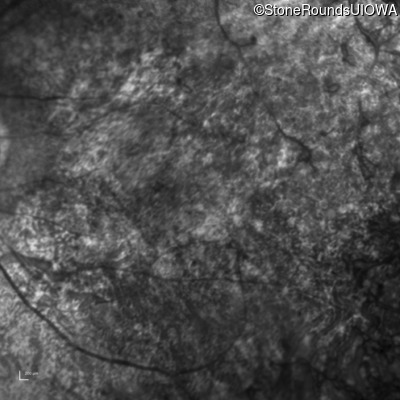

Infrared Fundus Photograph - Left - 20/250 sc

Exemplar